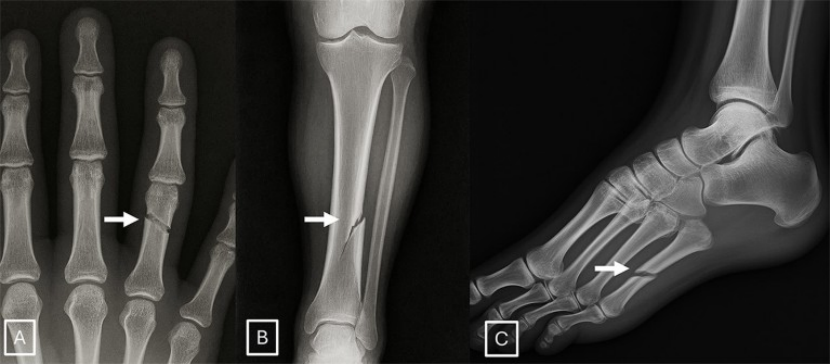

AI生成的X光片让科学家感到担忧。图片来源:北美放射学会

该研究设计了一项互动测试,旨在教会研究人员辨别AI生成的X光扫描图像与真实图像。它涵盖了AI生成的放射影像的一些典型特征,如骨骼过于光滑、脊柱异常笔直等。研究人员指出,除了培训放射科医生,数字水印等技术可以使识别真实图像变得更容易,政府机构主导的监管框架也可以这样做。